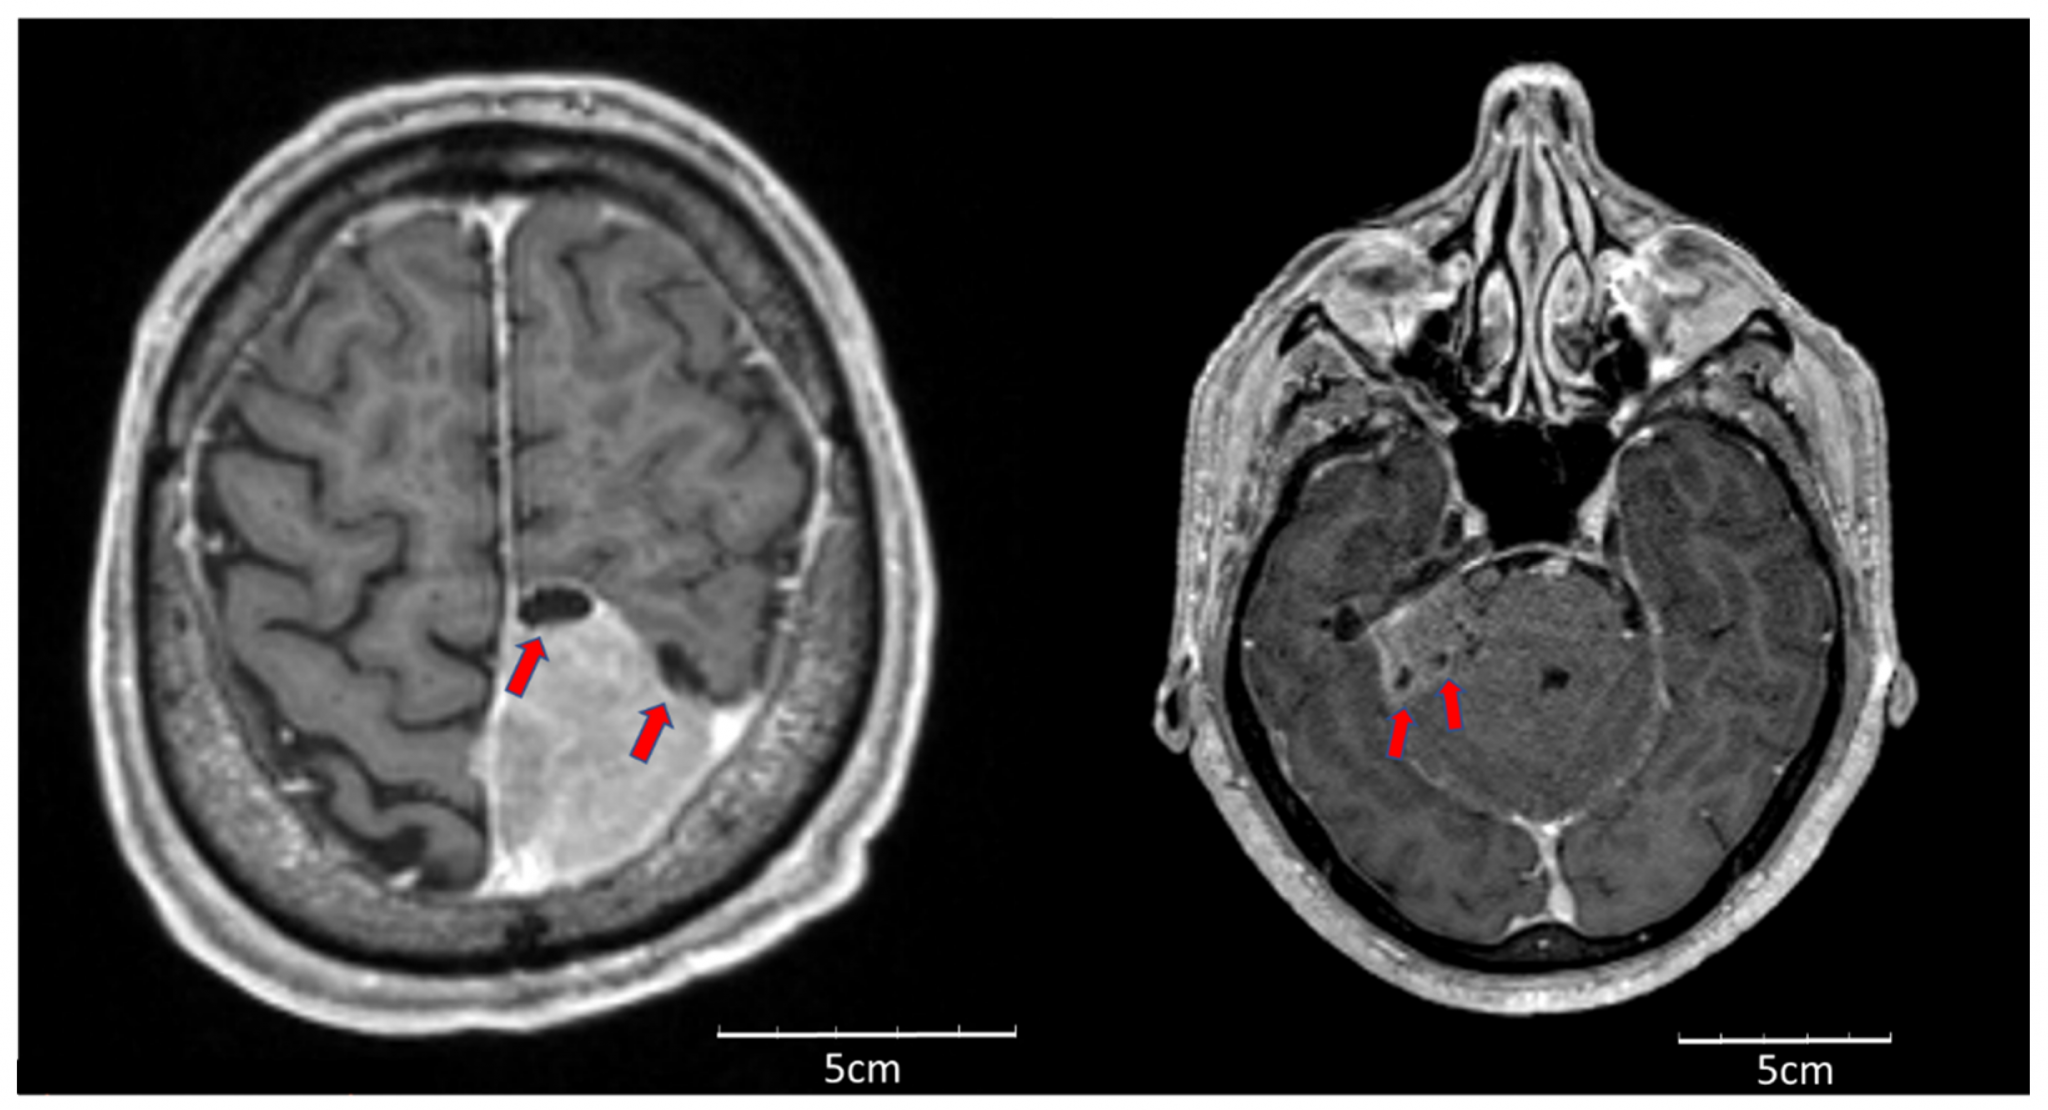

典型良性的腦膜瘤在女士身上較常見,非典腦膜瘤則較多見於男性,個案約為女性的兩倍,而年紀愈大及頭部曾接受放射治療的人都有較高的患病風險。至於判斷腦膜瘤是否非典型,磁力共振影像會提供一些線索,例如邊界較模糊、腫瘤周圍有水腫、頭骨甚至頭皮被入侵等。